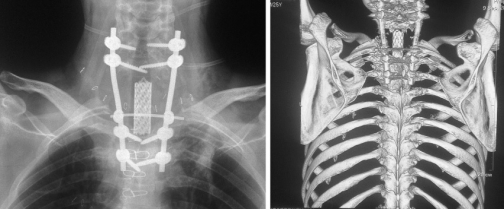

В декабре в НИИ онкологии имени Петрова Михаилу сделали две операции. Сначала удалили дужки пяти шейных позвонков (всего у человека семь шейных позвонков – прим.Авт.), зафиксировали затылочную кость, первый и седьмой шейные позвонки и первый грудной позвонок при помощи специальных титановых винтов и штанг. Операция длилась шесть часов.

Во время второй операции Михаилу удалили шейные позвонки, которые поражены опухолью. Вместо прежнего импланта вживили специальную сетчатую титановую трубку, заполненную костным цементом (протез тел позвонков – прим.ред. ).

Операцию по протезированию шейных позвонков проводили в два этапа. Сначала за 6 часов хирурги удалили пациенту дужки шейных позвонков — со второго по пятый, зафиксировали затылочную кость, а также 3 других позвонка - первый и седьмой шейные, а также первый грудной с помощью специальных титановых винтов и штанг. Во время второго этапа операции, длившегося 8 часов, мужчине удалили тела пяти шейных позвонков, пораженных опухолью (со второго по шестой), а также удалили установленный ранее в другой клинике имплантат. Затем хирурги заменили удаленные позвонки специальной сетчатой титановой трубкой, заполненной костным цементом — протезом тел позвонков.

Как говорят врачи, эта операция уникальна не только для российской, но и для мировой практики по нескольким причинам. Во-первых, по объему — хирурги полностью удалили 5 позвонков. Во-вторых, по локализации — вмешательство проводилось на шейном отделе позвоночника, где находится большое количество жизненно важных кровеносных сосудов, нервных структур, связанных с головным и спинным мозгом, - любое их повреждение может привести к инвалидизации или смерти. Кроме того, организм пациента в целом был ослаблен многолетней борьбой с онкологическим заболеванием, а во время самого вмешательства он потерял много крови — за два этапа почти 6 литров. В-третьих, хирурги впервые сделали такую операцию при метастазах. Раньше подобные вмешательства проводились только при первичных опухолях в верхнем шейном отделе позвоночника - сегодня в мире известно об 11 похожих случаях. Часть из них, опять же, выполнил тот же тандем петербургских хирургов — Дмитрия Пташникова, научного руководителя отделения нейроортопедии с костной онкологией РНИИТО им. Р.Р.Вредена, и Евгения Левченко, заведующего хирургическим торакальным отделением НИИ онкологии им. Н.Н.Петрова.

Дмитрий Пташников , профессор, научн. рук. отд. нейроортопедии с костной онкологией РНИИТО им. Р.Р. Вредена, зав. кафедрой травматологии и ортопедии СЗГМУ им. И.И. Мечникова: "Чтоб выполнить фиксацию, мы устанавливаем винты – либо за межпозвоночные суставы, либо ввинчиваем в тела позвонков – на этом строится ортопедия позвоночника. Затем винты соединяются штангами. Далее, вторым этапом резицировали оставшиеся тела позвонков и установили протез".